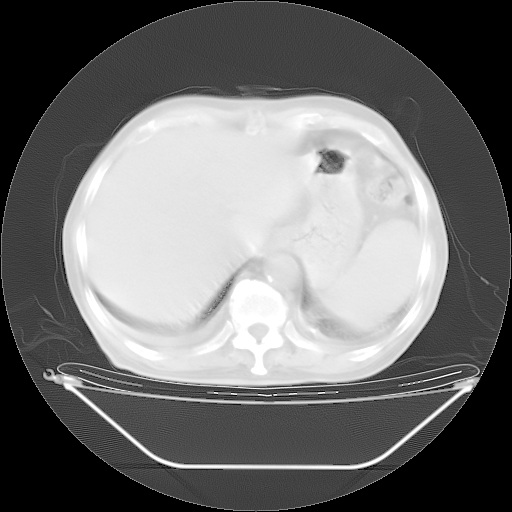

今天复查肺部CT,发现双肺广泛磨玻璃样改变。所以我把3月19日和5月9日相隔50天的肺部CT上传。请大家会诊。

5月9日肺部CT(在4月27日齐鲁医院肺部CT描述部分肺组织磨玻璃样改变,12天后肺组织广泛磨玻璃样改变)

2009年5月9日肺部CT

大致读了系列胸部CT:纵隔窗无明显异常,肺窗:从4、27至今:主要是双肺中下野外带可见毛玻璃样改变,目前处于急性肺泡炎阶段,至于原因考虑1、结替组织或胶原血管性疾病所致?2、恶性疾病如恶组在肺部所致的表现或细支气管肺泡癌?3、药物或其它原因如肺蛋白沉着症所致肺泡炎目前不太可能?总之,明天就去请我院的呼吸科、感染科、血液科和临免专家会诊哈。